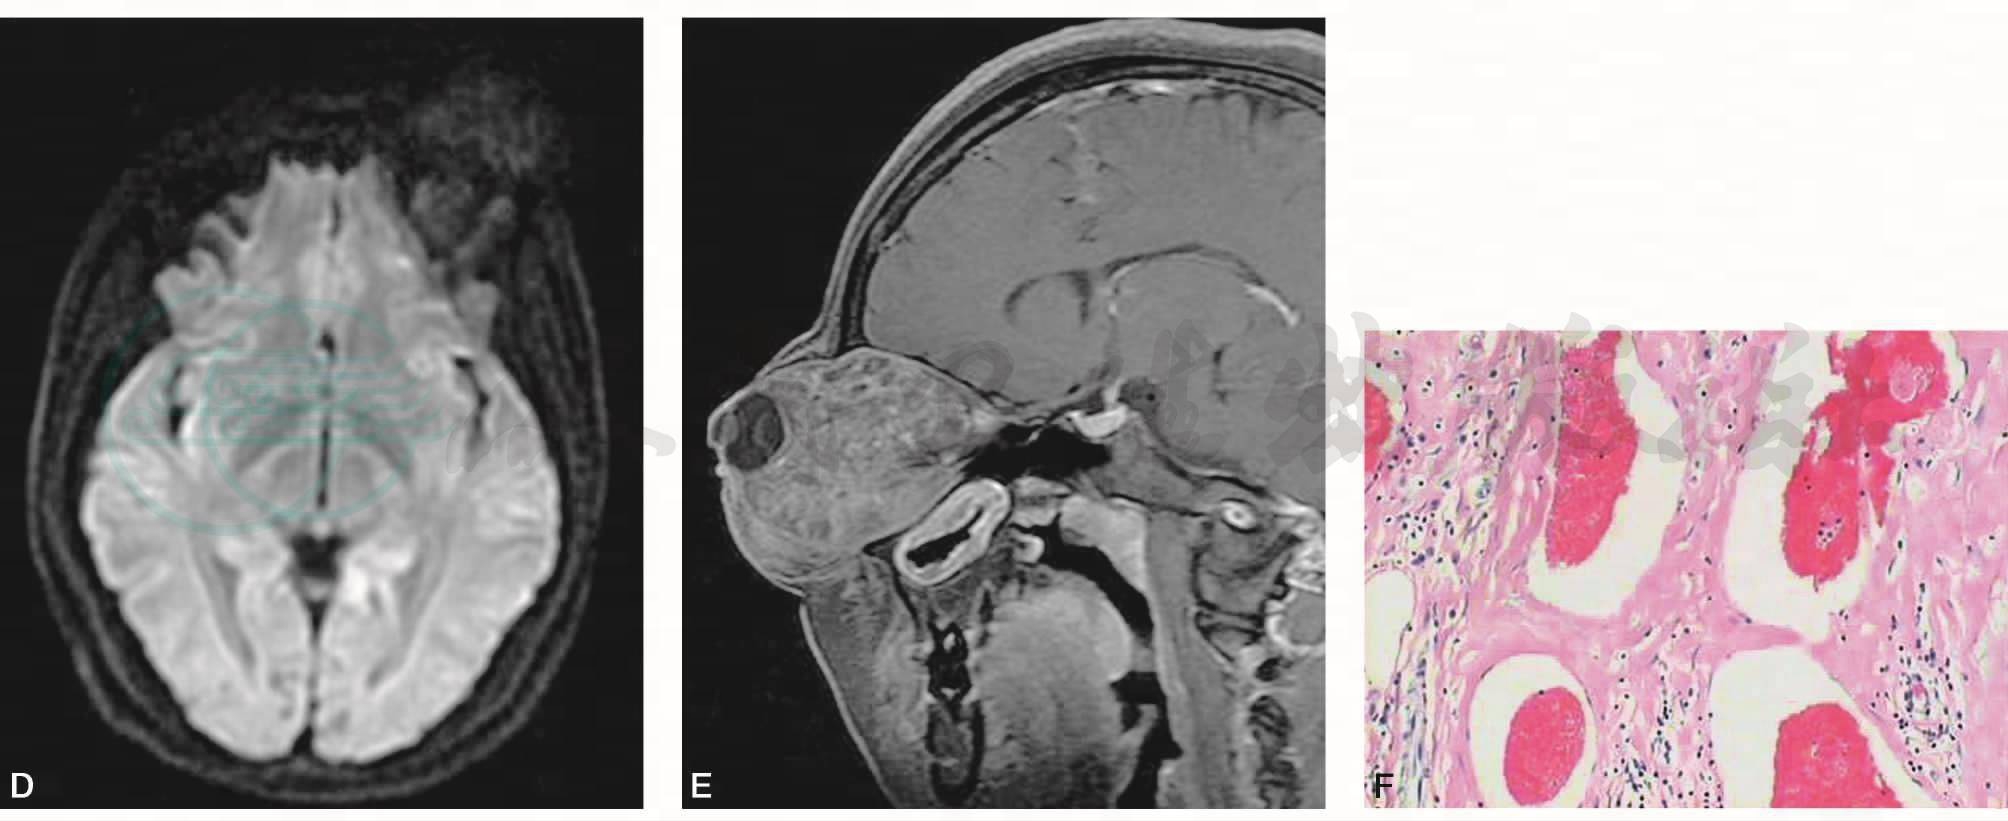

平扫示左眼球明显突出,左眼眶内充满软组织肿块,与肌肉相比,T2WI呈等信号,内可见多发小片及小结节状稍高-高信号,其高信号拟静脉石改变;T1WI呈等-明显高信号。病变包绕视神经,视神经被拉长,尚连续。病灶周边隐约见线状包膜,邻近骨质受压,眼眶扩大变形(图1A、B)。DWI显示病灶呈稍高信号改变(图1D)。Gd-DTPA增强扫描显示肿块呈渐进样不均匀明显强化,隐约可见内外直肌形态尚存在(图1C、E)。

图1 左侧眼眶血管瘤

A.压脂T1WI横断面;B.压脂T2WI横断面;C.增强横断面;D.DTI横断面;E.增强矢状面;F.病理(HE×200)

左眼送检组织7cm×5cm×4cm,表面似有包膜,切面暗红色,见血腔,镜下符合血管瘤。另眼球组织2.3cm×2.3cm×2cm,未见异常。